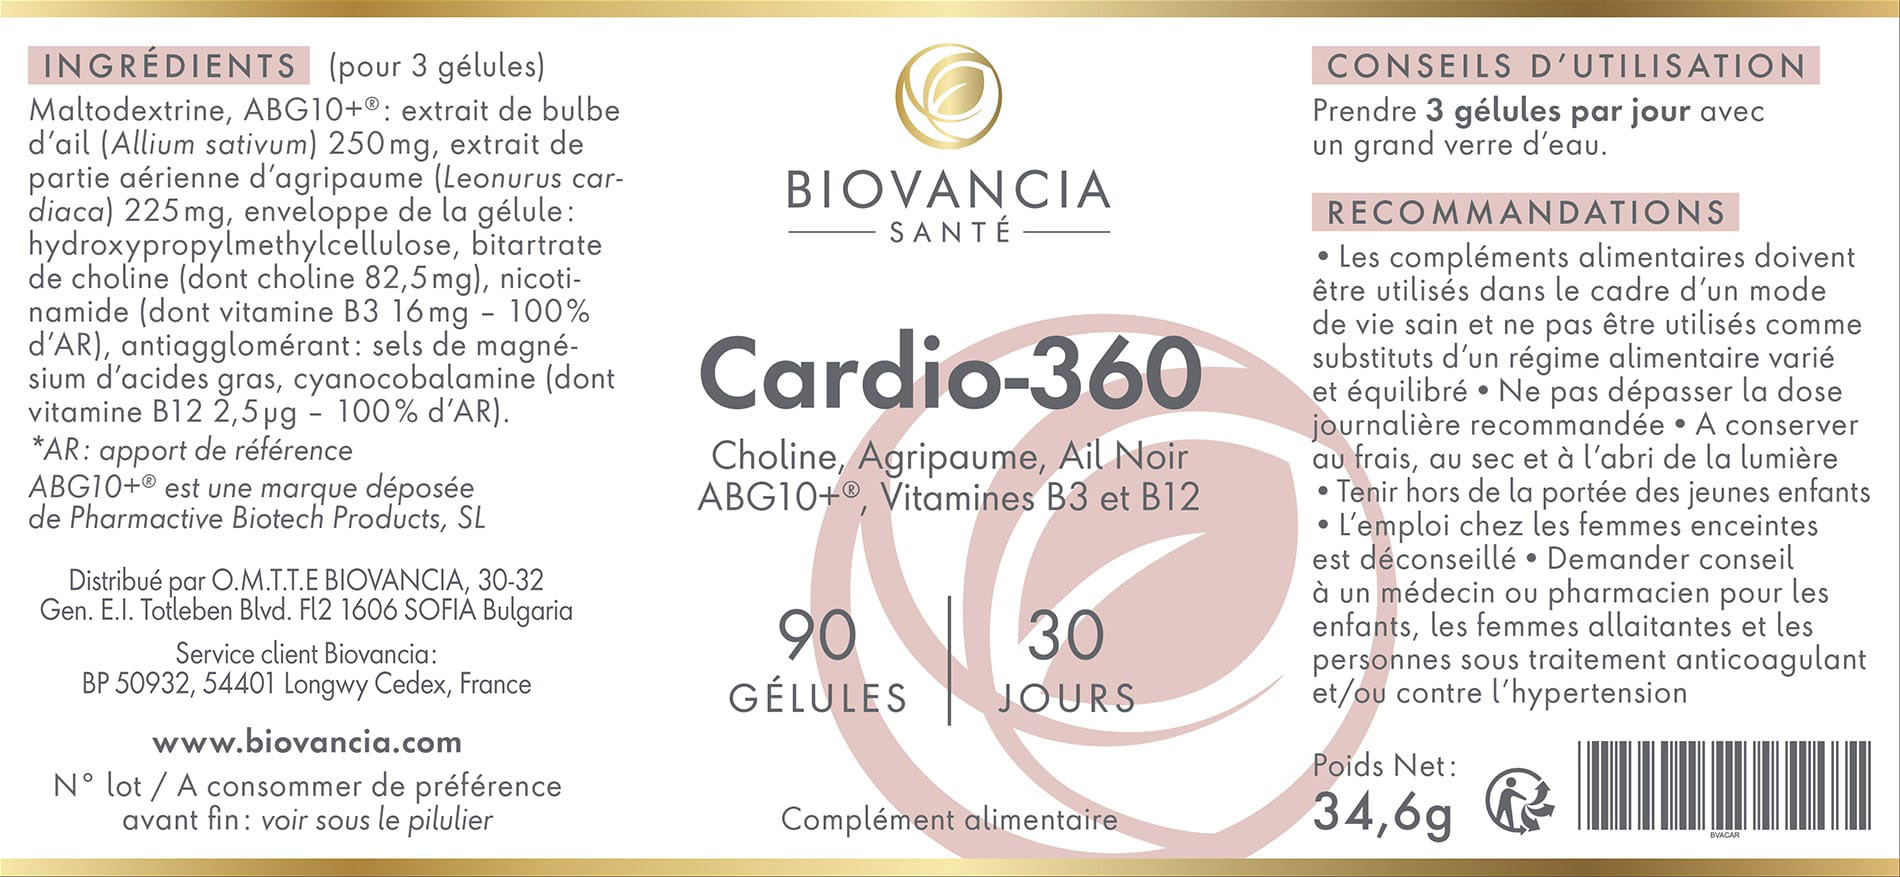

Cardio-360 composition

Cardio-360 contient cinq ingrédients actifs :

- choline

- ail noir (ABG-Plus®)

- l’agripaume

- la vitamine B-12

- la niacine